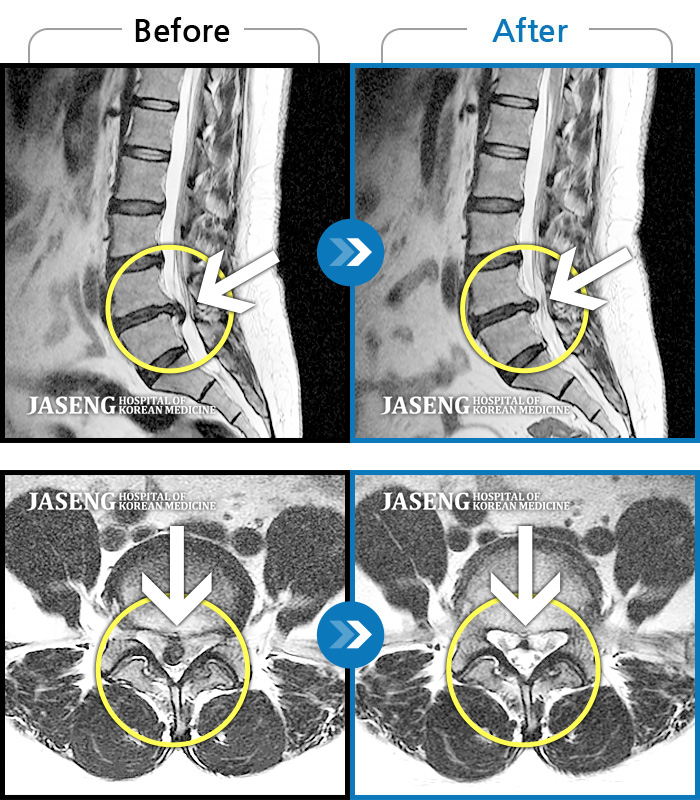

MRI 치료사례